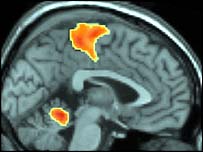

Đây là hình chụp não khi người phụ nữ giả vờ đạt tới đỉnh

Nó cho thấy mặc dù phụ nữ có thể lừa đàn ông khi họ giả vờ đạt đỉnh, nhưng nếu scan phần não bộ thì sẽ thấy sự khác biệt.

"Phụ nữ có thể giả vờ rất khéo là họ đạt đỉnh điểm, nhưng trong não thì khác. Việc ngưng kích hoạt các phần trong não có lẽ là yếu tố quan trọng nhất để đạt cực khoái."